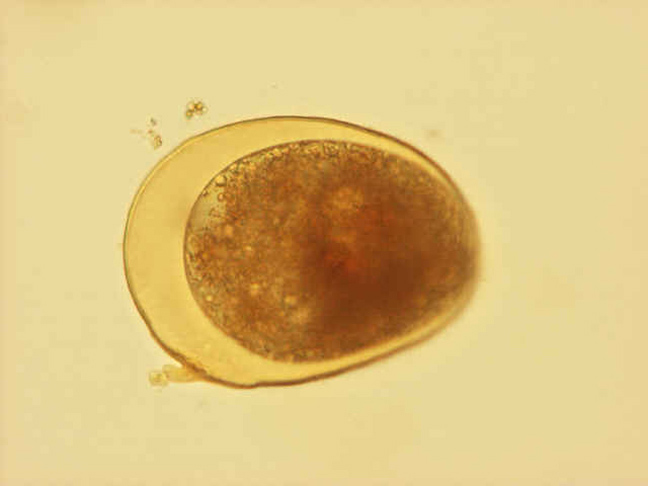

Fasciola Hepatica Fasciolopsis Buski